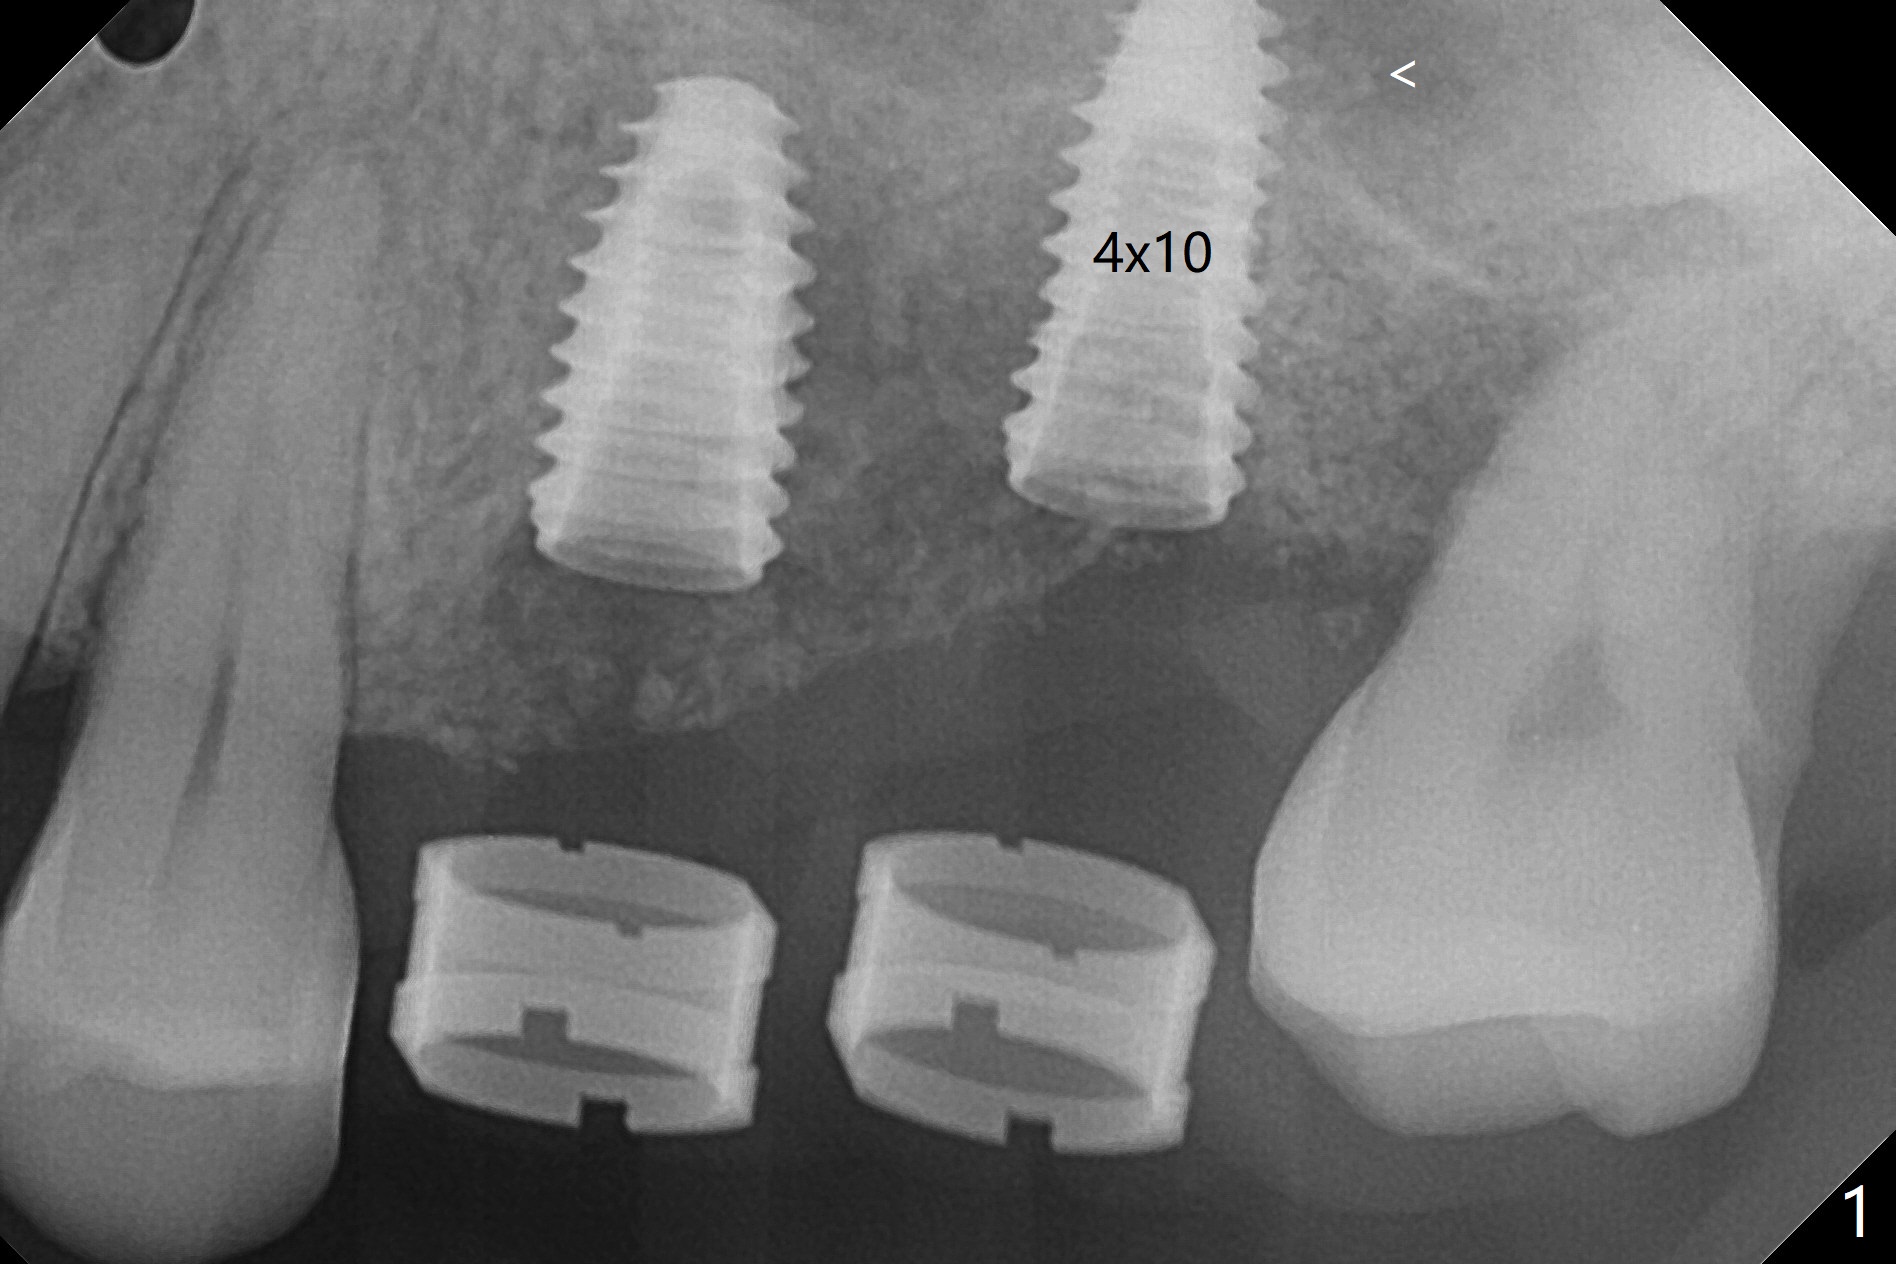

Fixture mount does not fit at #13 as an anchor. After 3.5x7.3 mm drill with 10.5 mm offset at #14, sinus lift drills (3.6x18 and 19 mm) are used. The sinus floor is intact. A 9 mm offset should be used. Following 4.0x10 mm dummy implant is placed for ~ 8.5 mm, the sinus floor is perforated while the sinus membrane is intact. After water lift, PRF membrane and allograft are inserted and pushed upward with the 4.0x10 mm dummy implant for ~ 10 mm (Fig.1). One more piece of PRF membrane and bone graft are lifted with a 4.5x10 mm dummy implant. A small dose of bone graft is elevated with a definitive implant (Fig.2,3, 5x10 mm). Is there enough bone to cover the apical part of the implant when the latter heals? When the patient returns for restoration 4.5 months postop, local oral hygiene is not good with light gingival erythema. There is tenderness when the healing abutment is being removed. It appears that osteointegraton is to occur; the mesial bone density is low (Fig.4 *). Healing abutment should be not placed when sinus lift repeatedly fails. In fact the implant is removed with the healing abutment 6.5 months postop. The buccal plate is missing, while the sinus floor is intact. Ossogen is placed, covered by Osteogen plug and sutured with PGA (Fig.5). The buccal plate remains concave 8 days postop (Fig.6 B). In the 4th trial, incision will be made, flaps dissected extensively with suture fixation. The existing guide is used to start osteotomy with point drill, followed by bone expansion. Reload the guide to place a narrower implant 4 or 4.5 mm with cover screw, and place sticky bone buccal. The latter is covered with PRF and suture. If stability is insufficient, perforate the sinus floor. Place a cemented abutment at #13 to hold periodontal dressing. Use profile drill if needed.Return to Upper Molar Immediate Implant, Trajectory II Xin Wei, DDS, PhD, MS 1st edition 08/13/2019, last revision 02/13/2021